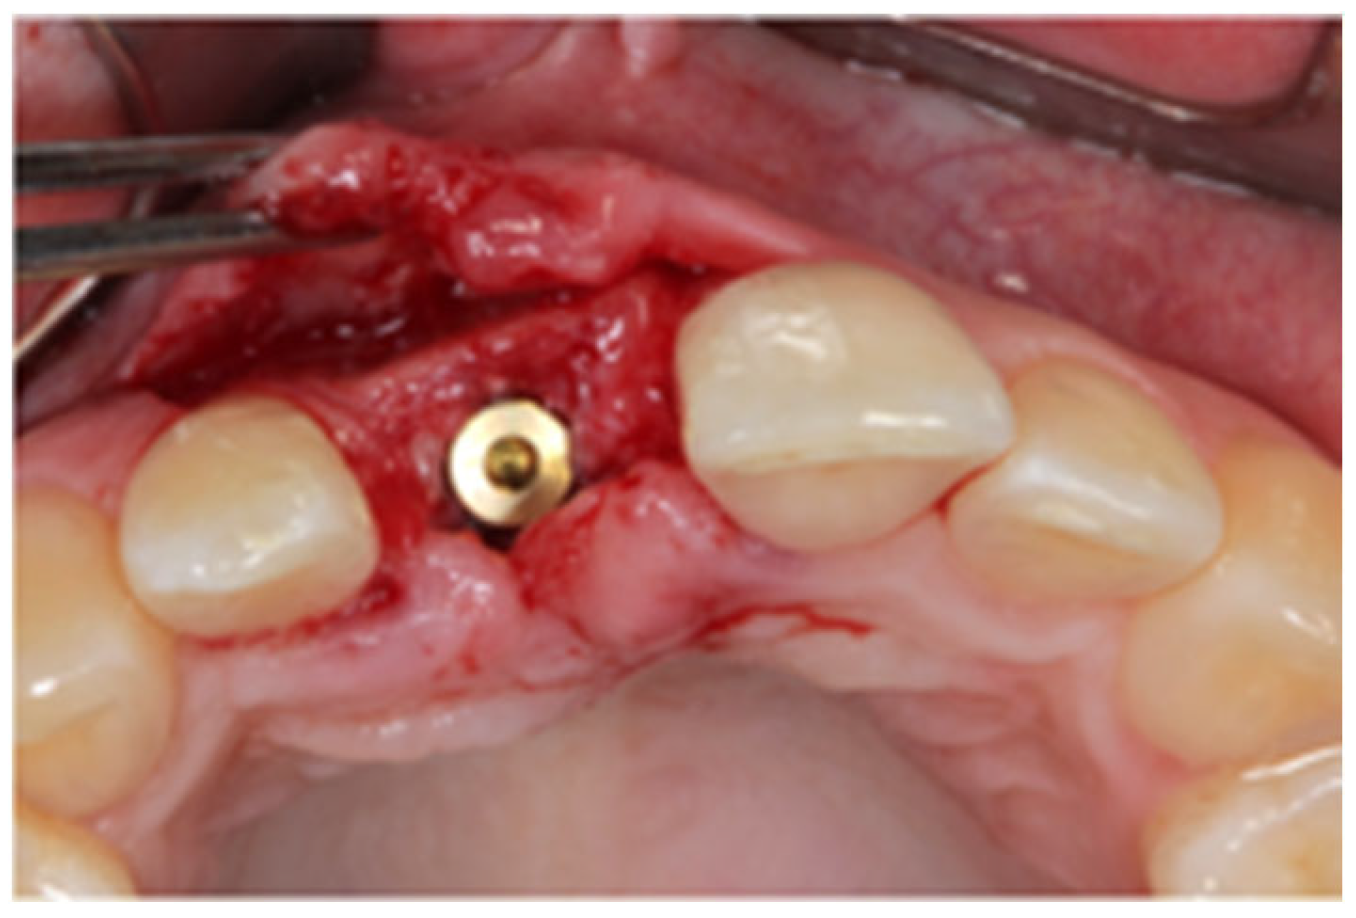

2.1. Surgical Technique